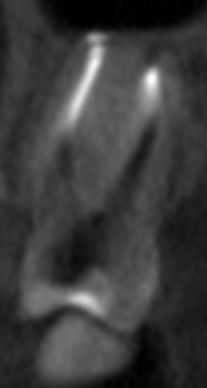

Вчера сделал КТ и стало понятно, что в двух корнях выведен материал за верхушку что аж у корней шляпки появились, а другой корень недопломбирован до конца на несколько миллиметров. Я читал что материалы выводить за апекс в принципе нельзя и это чревато, неужели пульсация над бровью и в области виска связана с этим? Он же и после удаления зуба там останется, как я понял. Где этот материал находится судя по снимкам? Не может ли он как-то влиять на тройничный нерв (не разбираюсь с этим)?

Screenshot_4.png.5e7921a698b28cc04edfe2a9ef1ab7c6.pngScreenshot_5.png.3786d148a30936dc0c8bb6475d7b25c7.pngScreenshot_6.png.cac5adb8499290207c4c9a6019795985.pngScreenshot_7.png.c63e3bf191b149a107f5b4664370a2df.png

Подскажите, пожалуйста, что тут можно сделать и насколько опасен этот выведенный материал. Вроде бы пломбировали Thermafil AH+.